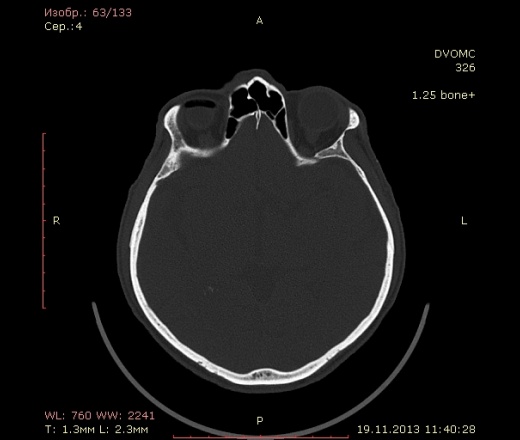

49 лет. Травма около месяца назад - удар в верхнюю челюсть спереди, так сказать...под нос.... в субнозальную область:-) Жалобы только на небольшие боли в месте травмы.

Воздух в правой орбите - под веком или нет? При моргании мог он так туда попасть и так распределиться? Или в резутьтате травмы из пазухи как-то попал и не уходит?

Мелкие пузырьки воздуха попадались, но такое количество и в виде кольца...Это нормально?

Это циркляжная лента для ретинопексии. Накладывают на глаз как пояс при отслойке сетчатки. Расспросите больного.